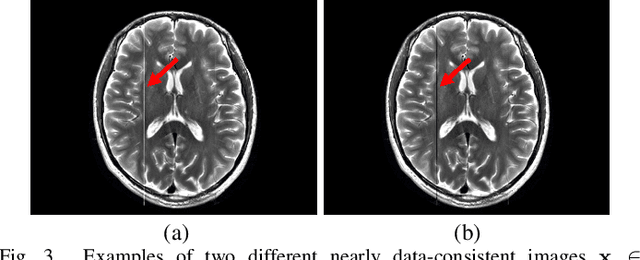

Abstract:Ill-posed linear inverse problems appear frequently in various signal processing applications. It can be very useful to have theoretical characterizations that quantify the level of ill-posedness for a given inverse problem and the degree of ambiguity that may exist about its solution. Traditional measures of ill-posedness, such as the condition number of a matrix, provide characterizations that are global in nature. While such characterizations can be powerful, they can also fail to provide full insight into situations where certain entries of the solution vector are more or less ambiguous than others. In this work, we derive novel theoretical lower- and upper-bounds that apply to individual entries of the solution vector, and are valid for all potential solution vectors that are nearly data-consistent. These bounds are agnostic to the noise statistics and the specific method used to solve the inverse problem, and are also shown to be tight. In addition, our results also lead us to introduce an entrywise version of the traditional condition number, which provides a substantially more nuanced characterization of scenarios where certain elements of the solution vector are less sensitive to perturbations than others. Our results are illustrated in an application to magnetic resonance imaging reconstruction, and we include discussions of practical computation methods for large-scale inverse problems, connections between our new theory and the traditional Cram\'{e}r-Rao bound under statistical modeling assumptions, and potential extensions to cases involving constraints beyond just data-consistency.